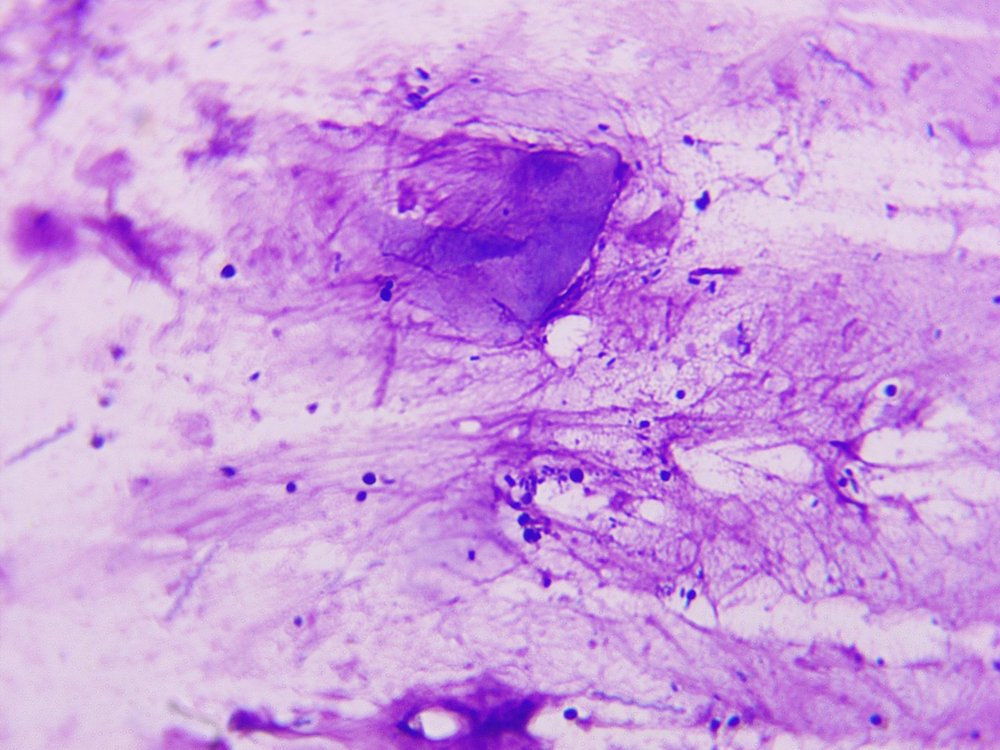

@Zosia , посмотрите, пожалуйста, фото анализа (мазок из клюва). Сдавала цитологию в чел.лаборатории. В заключении написано : "найдено элементы дрожжеподобных грибов, густо кокковую флору (стрептококки, стафилококки)." Лаборанты сказали, что еще что-то есть, но они не знают, что это...Точно, не трихомонады.  Может, Вы по фото увидете.

изображение_viber_2020-06-23_13-12-23.jpg

Сдавала цитологию в чел.лаборатории. В заключении написано : "найдено элементы дрожжеподобных грибов, густо кокковую флору (стрептококки, стафилококки)." Лаборанты сказали, что еще что-то есть, но они не знают, что это...Точно, не трихомонады.

Это исследования помёта или мазка из зёва?

По этому материалу необходим бак.посев чтобы конкретизировать бактерии и определить к каким препаратам они чувствительны.